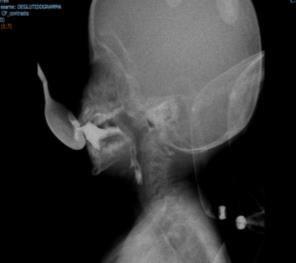

Videofluoroscopy

ORAL PREPARATORY PHASE IN EATING SOLID FOOD

✓ Loss of food out mouth, pushed out with tounge

✓ Food in anterior sulcus

✓ Limited tongue movement

✓ Problem about turning the food into bolus formation

✓ Food in valleculae and pharynx,

pre swallow

✓ Jaw grading inappropriate

ORAL PREPARATORY PHASE IN DRINKING LIQUID FOOD

✓ Loss of food out mouth

✓ Liquid in anterior sulcus

✓ Food pushed out with tounge

✓ Food in valleculae and pharynx, pre swallow

ORAL PROPULSIVE. PHASE:

✓ Food or liquid remains in anterior and/or lateral sulcus

✓ Food or liquid remains on floor of mouth

✓ Limited posterior tongue movement

✓ Reduced base of tongue action

✓ Tongue-soft palate contact incomplete

✓ Multiple swallows per bolus

✓ Delayed oral transit time

PHARYNGEAL PHASE

✓ Nasopharyngeal regurgitation

✓ Slow bolus passage through Pharynx

✓ Reduced pharyngeal contraction/motility

✓ Residue cleared with next swallow

✓ Residue not cleared

✓ Reduced hyolaryngeal execursion

✓ Penetration to underside of epiglottis

✓ Penetration to laryngeal vestibule

✓ Aspiration before, during and after swallow

✓ Aspiration respons: not effective cough, no cough – silent aspiration

ESOPHAGEAL PHASE

✓ Slow bolus passage through UES

✓ Residual on UES

✓ Cricopharyngeal dysfunction

✓ Slow bolus passage through esophagus